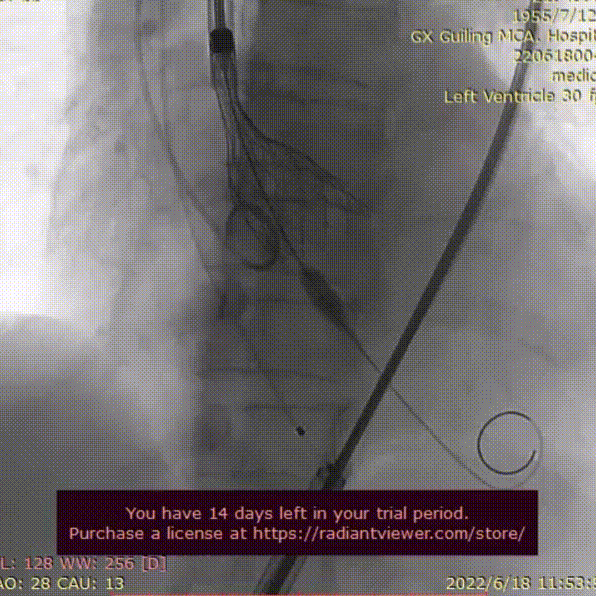

AV29瓣膜定位

AV29瓣膜释放到工作位

AV29瓣膜回收调整后定位

AV29瓣膜再次释放到工作位

AV29瓣膜释放后造影,形态良好

本例手术为中度钙化三叶式病变中度主动脉瓣狭窄并重度关闭不全TAVR手术,外周入路走行迂曲,散在钙化,预估术中入路穿刺难度较大,存在入路血管损伤及相关并发症风险,术前手术团队对患者进行了全面细致的评估,确定假体瓣膜锚定区域范围,制定术前释放策略,入路穿刺规范操作,小心通过,避免了入路血管损伤及相关并发症。王海永主任团队通力配合、精准释放,充分利用TaurusElite可回收功能,在瓣膜释放至2/3时,多角度评估瓣膜植入深度、锚定力以及冠脉灌注情况,确认瓣膜植入深度合适、锚定力稳定,缓慢逐个脱钩,进行瓣膜释放,瓣膜释放后造影显示瓣膜膨胀良好,无明显瓣周漏,手术圆满完成。